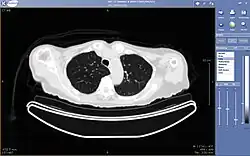

Teleradiology

Teleradiology is the ability to send radiographic images (x-rays, CT, MR, PET/CT, SPECT/CT, MG, US...) from one location to another.[58] For this process to be implemented, three essential components are required, an image sending station, a transmission network, and a receiving-image review station. The most typical implementation are two computers connected via the Internet. The computer at the receiving end will need to have a high-quality display screen that has been tested and cleared for clinical purposes. Sometimes the receiving computer will have a printer so that images can be printed for convenience.

The teleradiology process begins at the image sending station. The radiographic image and a modem or other connection are required for this first step. The image is scanned and then sent via the network connection to the receiving computer.

Today's high-speed broadband based Internet enables the use of new technologies for teleradiology: the image reviewer can now have access to distant servers in order to view an exam. Therefore, they do not need particular workstations to view the images; a standard personal computer (PC) and digital subscriber line (DSL) connection is enough to reach keosys central server. No particular software is necessary on the PC and the images can be reached from wherever in the world.

Teleradiology is the most popular use for telemedicine and accounts for at least 50% of all telemedicine usage.